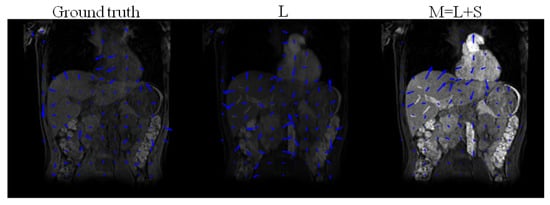

4.1. Low-Rank Plus Sparse Image Decomposition

4.2. Low-Rank Plus Sparse Image Decomposition from Undersampled -Space Data